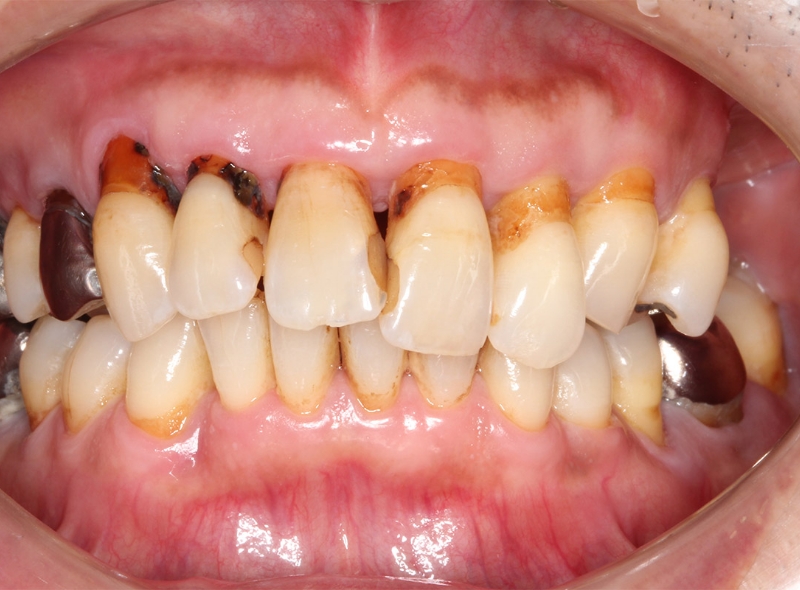

CASE 歯周病治療症例

Before

| 年齢 | 59歳 |

|---|---|

| 性別 | 男性 |

| 症状 | 歯がグラグラする。歯茎が腫れる。 |

| 治療法 | 歯周病治療 補綴治療(被せ物) |

| 費用 | 症例による(基本的には保険治療で可能) |

| 通院回数 | 症例による |

| リスク・副作用 | 知覚過敏症状がでることがある |

| 備考 | 歯を支える骨が高度に吸収していたが、歯周病治療と被せ物の治療により改善し、治療完了。 |